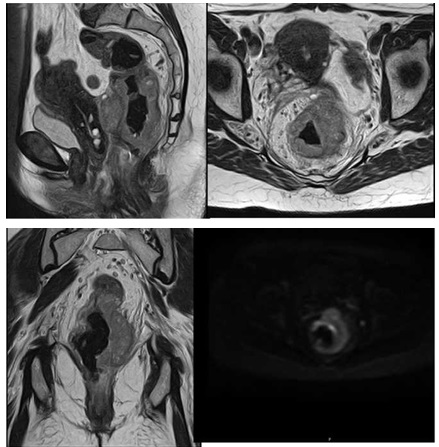

Imágenes de resonancia magnética